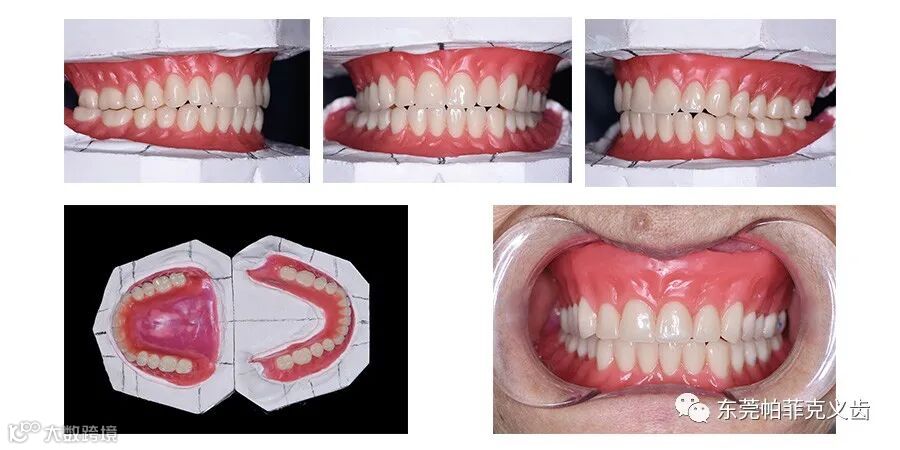

【案例展示】